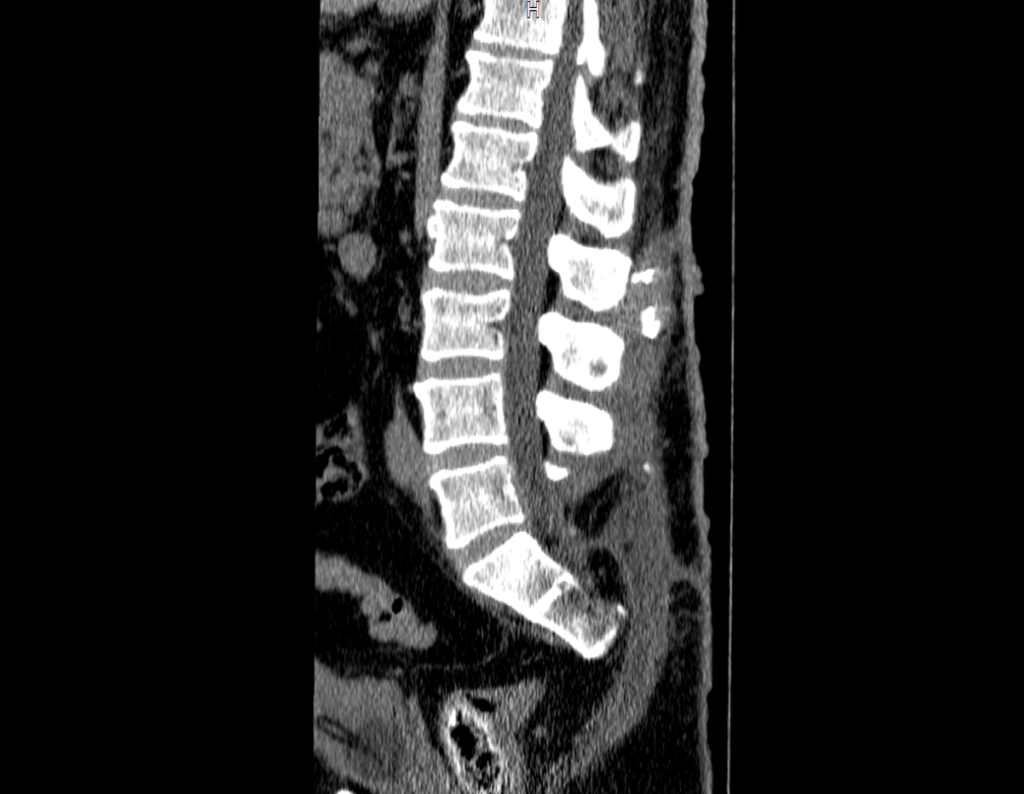

Tomografia Computadorizada (TC): A tomografia evidenciou o limite proximal da lesão infiltrando a musculatura paravertebral esquerda, com calcificação próxima à face externa da lâmina. Cortes axiais mostraram a lesão presa à asa do ilíaco esquerdo, com inúmeras calcificações e protrusão em direção à pele. A lesão acometia a parede externa do hemisacro e da pelve esquerda, com superfícies anfractuosas.

Reconstrução 3D em TC: As imagens em 3D da bacia em diversas posições mostraram a extensão e localização da lesão, afetando o processo espinhoso de S2 e a região posterior do ilíaco esquerdo. O comprometimento das lâminas e do processo espinhoso de S3 e da região sacro-ilíaca foi claramente visualizado.